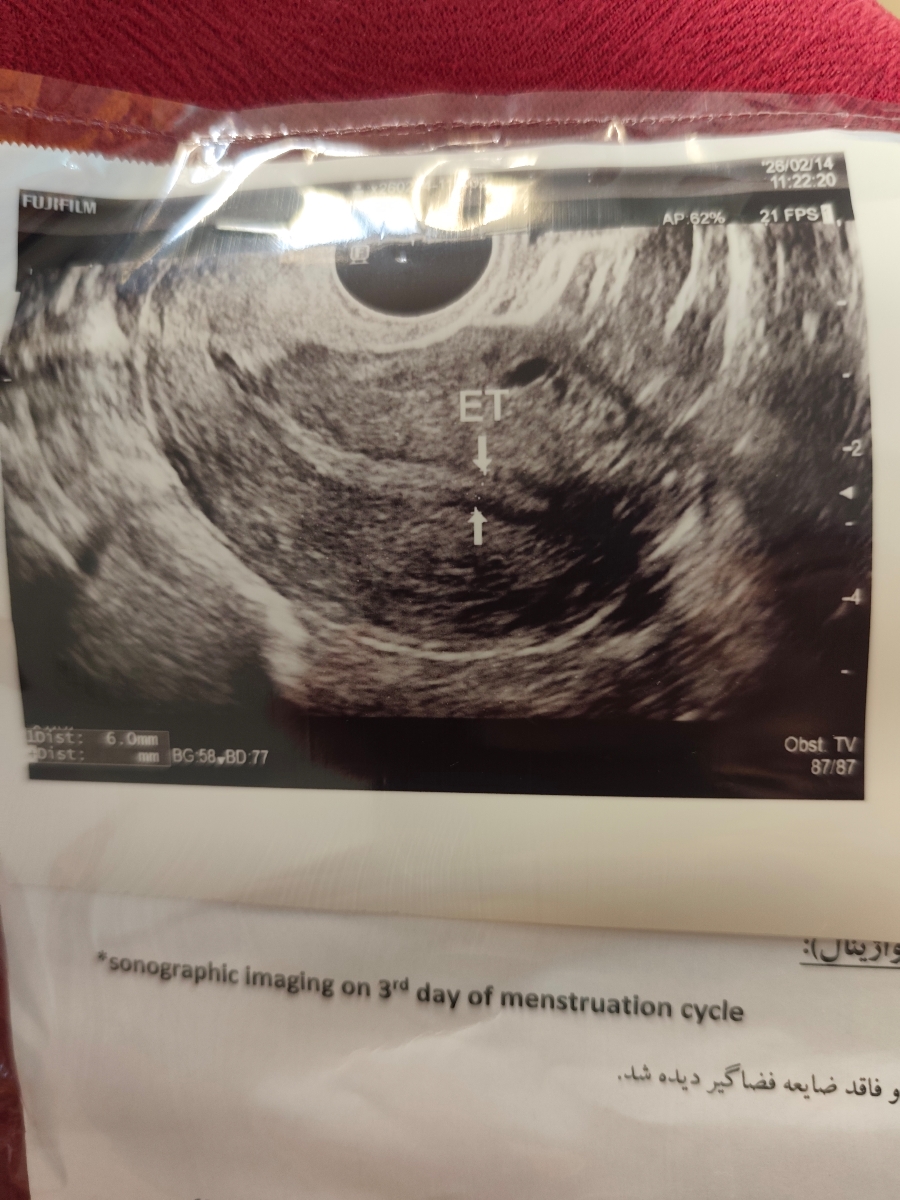

سوال دوم اینکه من رفتم سونو داخلی روز سوم پریود دادم ، دکتر گفتن تنبلی تخمدان و چسبندگی دارم میزان چسبندگی رو نمیدونم چقدره . من یکسال توی اقدام بودم اضافه وزن هم دارم . دکتر به من رژیم غذایی دادن و پیاده روی

و قرص لتروزول و متفورمین هم دادن بهم و من این قرص هارو دارم مصرف میکنم